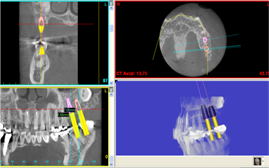

骨再生した箇所にインプラントを埋入します。

CTで治療計画を綿密に練ったうえで行いました。

インプラント埋入

インプラント埋入後のレントゲン画像です。